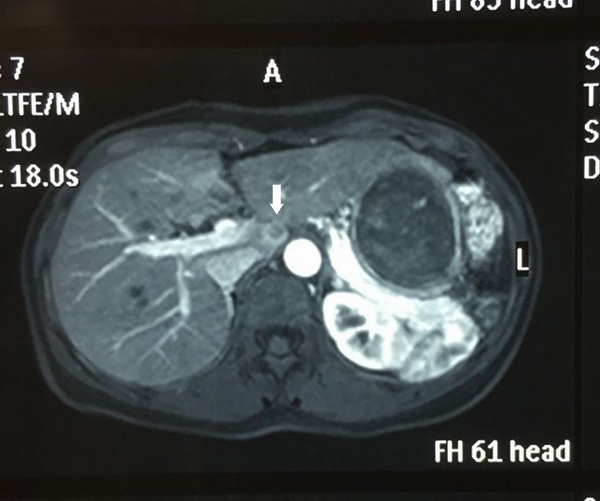

(箭头处为Ⅶ、Ⅷ段交界处肿瘤

(箭头处为尾状叶肿瘤)

619日,由陈进宏教授、贾户亮副教授、陆录和朱文伟主治医生组成的医疗团队,在钦伦秀主任的指导下,为1例结肠癌术后肝转移的患者成功施行了腹腔镜下肝脏转移瘤切除术。该患者的病灶分别处于肝脏尾状叶和Ⅶ、Ⅷ段交界处,其中尾状叶处肿瘤位置深,紧邻血管。由于患者首次结肠癌手术为开放手术,腹腔内粘连较严重,因此实施腹腔镜手术难度极大。钦伦秀主任带领团队术前拟定详尽的治疗方案,术中精细操作,顺利完成手术。同日,该团队还为1例结肠癌肝转移患者施行了腹腔镜下结肠癌和肝脏转移灶同期切除术。两名患者术后恢复顺利,近日顺利出院。此次成功施行的肝脏尾状叶肿瘤腹腔镜切除术,标志着华山医院普外科肝胆外科专业组已能开展所有肝段肿瘤的腹腔镜手术,居全国领先行列。